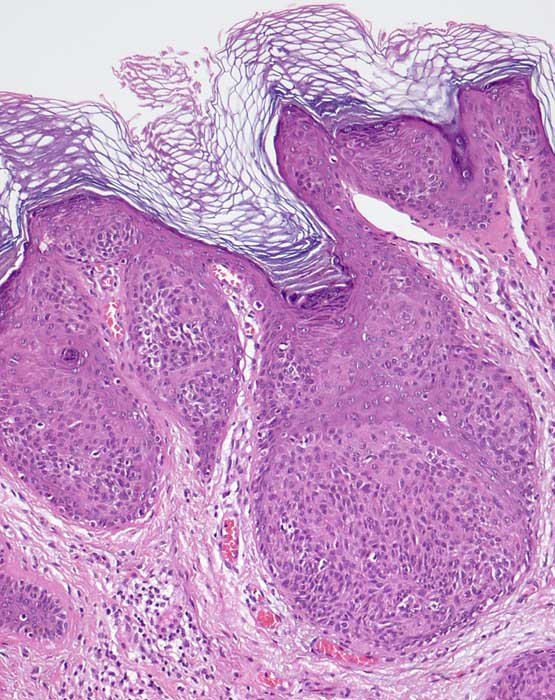

Klonale seborrhoische Warze (Borst Jadassohn Phänomen)

Hyperplastische Epidermis mit umschriebenen Epithelnestern.

Das Borst Jadasshon Phänomen mit intraepidermalen Nestern kann bei verschiedenen Tumorarten auftreten: Hidroacanthoma simplex (intraepidermales Porom), seborrhoische Warze, Morbus Bowen.

Histologie

100